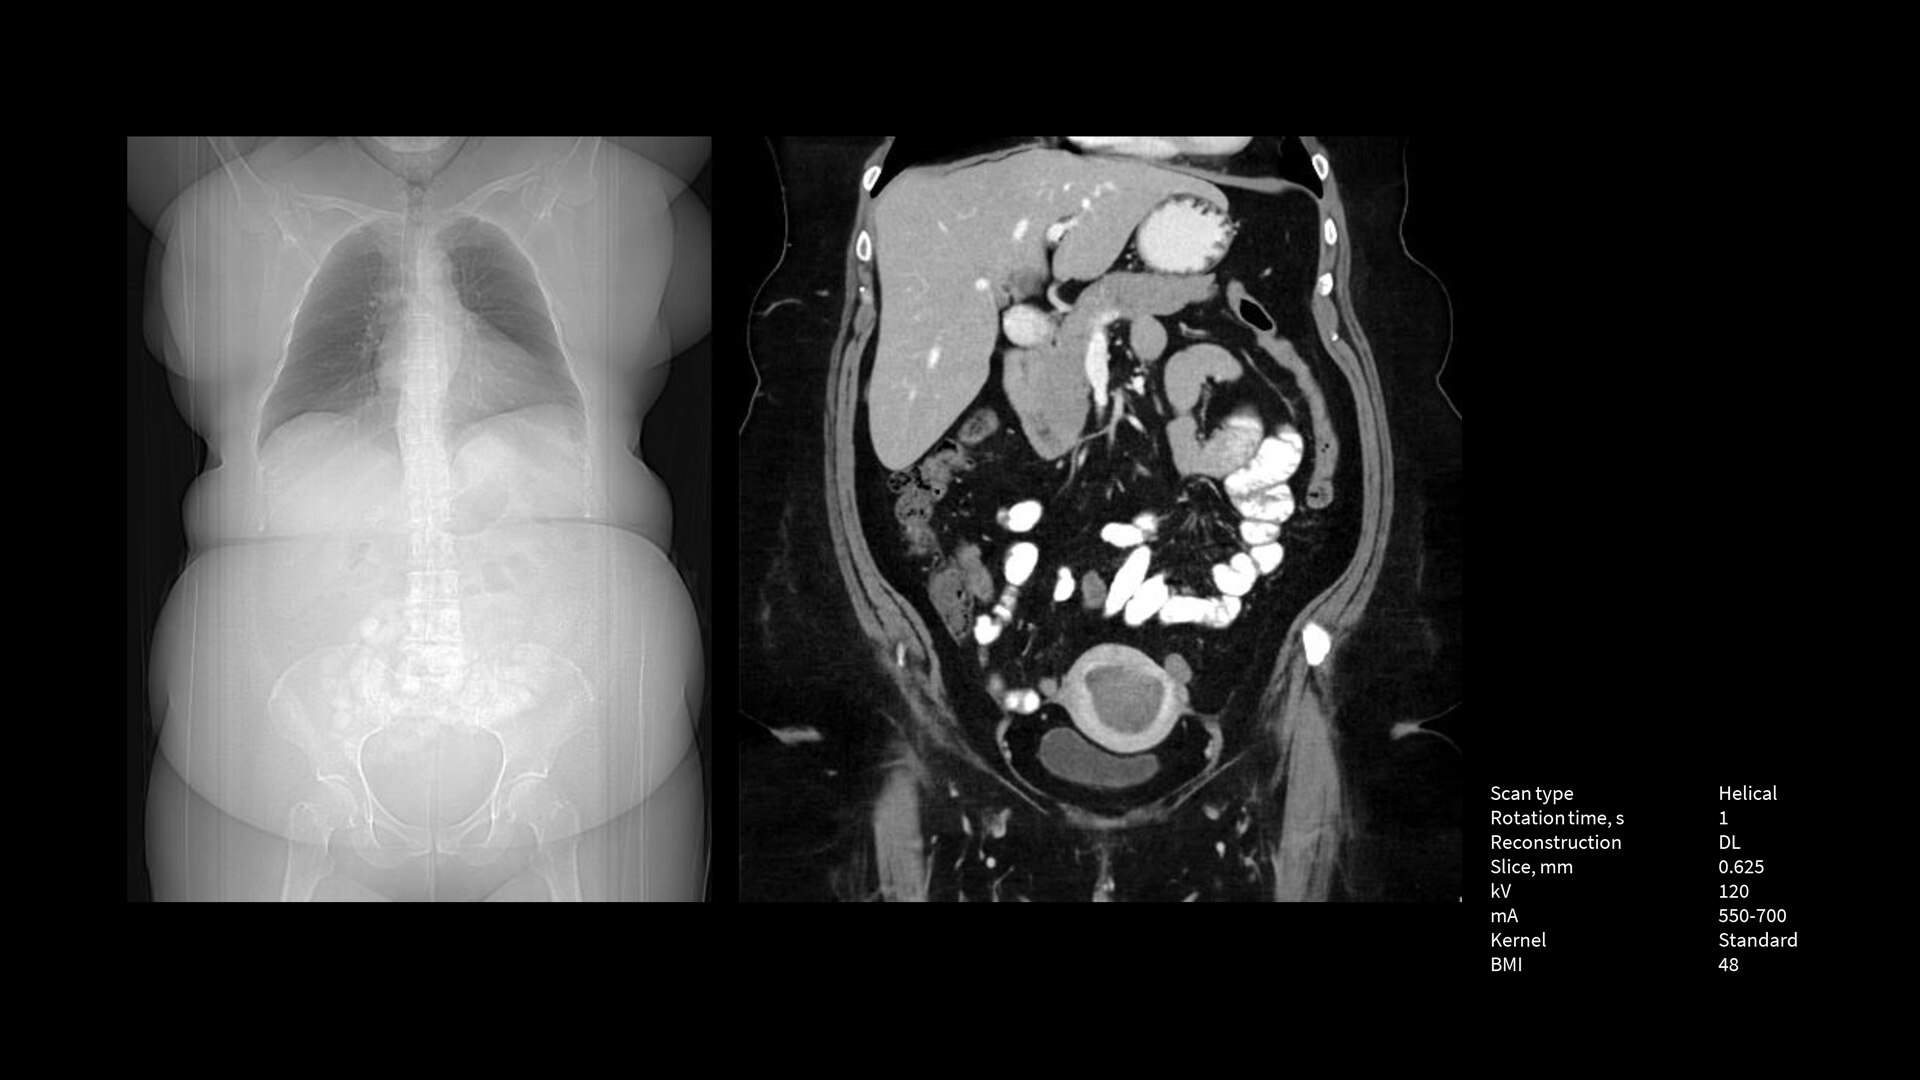

The Revolution Apex platform was built with exceptional technologies throughout the imaging chain and with an Effortless Workflow model of efficiency to help you meet your imaging challenges. To meet tomorrow’s needs, we’ve built it with scalable detectors that allow you to take your practice to the next level at any time. The Revolution Apex platform is the powerful, adaptable technology you need to lead CT now and into the future.

Scalable Clarity Detector

The Revolution Apex platform has a modular design that allows for hardware scalability. You can start with Revolution Apex Select with a 40mm detector and in the future, when you need to grow your service line, you can scale the detector up to 160mm.